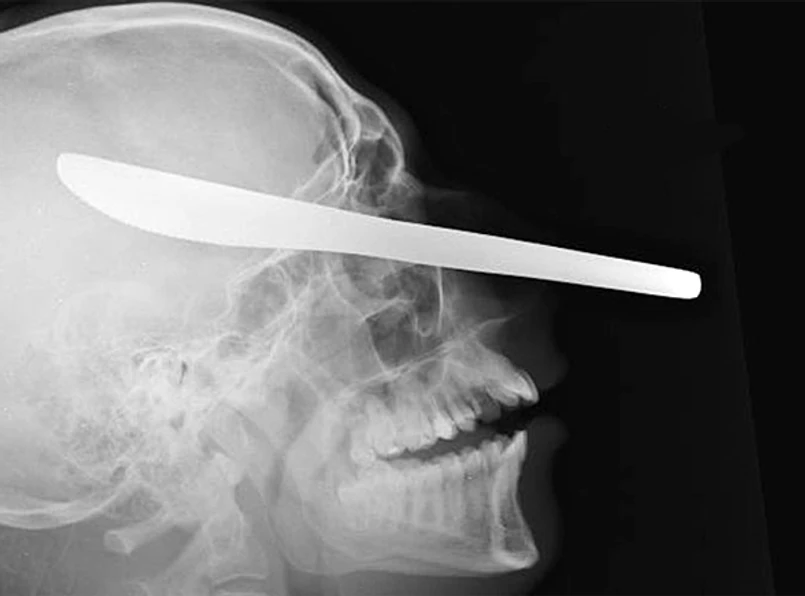

Michał C. nie chciał zapłacić prostytutce, więc jej chłopak dźgnął go nożem do smarowania masła. Nóż utkwił w okolicy oka, 2,5 cm od mózgu. Michał C. przeżył atak. Mężczyzna, który go napadł, właśnie usłyszał wyrok.